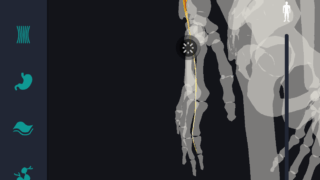

はじめに 本記事では、人体解剖学における専門的な部位の知識を始めに、効果的な勉強法についてご説明します。 人体解剖学では様々な器官や筋肉、骨の名称を覚えるだけではなく、体のどの位置に存在するのかまで覚えなければなりません。そのため、できるだ...